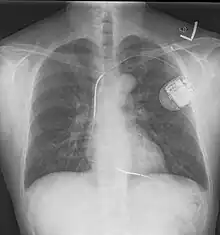

An implantable cardioverter-defibrillator (ICD) or automated implantable cardioverter defibrillator (AICD) is a device implantable inside the body, able to perform defibrillation, and depending on the type, cardioversion and pacing of the heart. The ICD is the first-line treatment and prophylactic therapy for patients at risk for sudden cardiac death due to ventricular fibrillation and ventricular tachycardia.[1]

The process of implantation of an ICD system is similar to implantation of a artificial pacemaker. In fact, ICDs are composed of an ICD generator and of wires. The first component or generator contains a computer chip or circuitry with RAM (memory), programmable software, a capacitor and a battery; this is implanted typically under the skin in the left upper chest. The second part of the system is an electrode wire or wires that, similar to pacemakers, are connected to the generator and passed through a vein to the right chambers of the heart. The lead usually lodges in the apex or septum of the right ventricle.[6]

Just like pacemakers, ICDs can have a single wire or lead in the heart (in the right ventricle, single chamber ICD), two leads (in the right atrium and right ventricle, dual chamber ICD) or three leads (biventricular ICD, one in the right atrium, one in the right ventricle and one on the outer wall of the left ventricle). The difference between pacemakers and ICDs is that pacemakers are also available as temporary units and are generally designed to correct slow heart rates, i.e. bradycardia, while ICDs are often permanent safeguards against sudden life-threatening arrhythmias.

Initially ICDs were implanted via thoracotomy with defibrillator patches applied to the epicardium or pericardium. The device was attached via subcutaneous and transvenous leads to the device contained in a subcutaneous abdominal wall pocket. The device itself acts as an electrode. Most ICDs nowadays are implanted transvenously with the devices placed in the left pectoral region similar to pacemakers. Intravascular spring or coil electrodes are used to defibrillate. The devices have become smaller and less invasive as the technology advances. Current ICDs weigh only 70 grams and are about 12.9 mm thick.